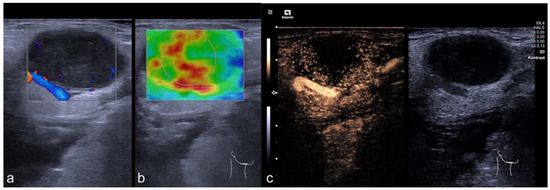

2.2. Imaging Protocol

2.3. Perfusion Analysis

3.5. CEUS